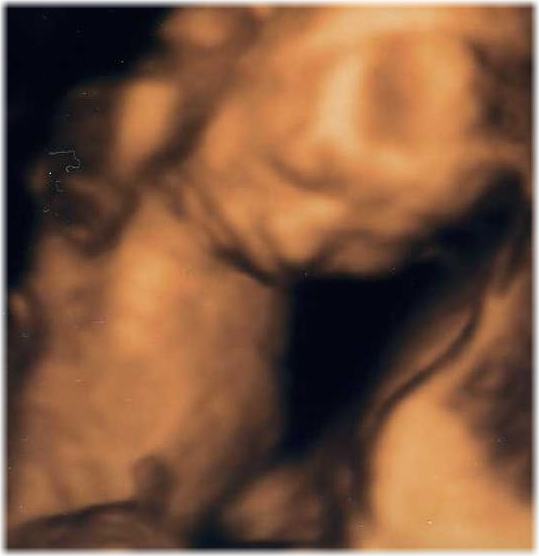

4D画像のお腹のBABYです。

BABY

長野には無いのでパソコンで探し群馬県へ行ってきました。

月1で行っています。

だがまだ性別が分からず1回目は6ヶ月の時でまだ分かりづらく

先月は逆子で見えづらく今度は最後で1月中旬に行きます。